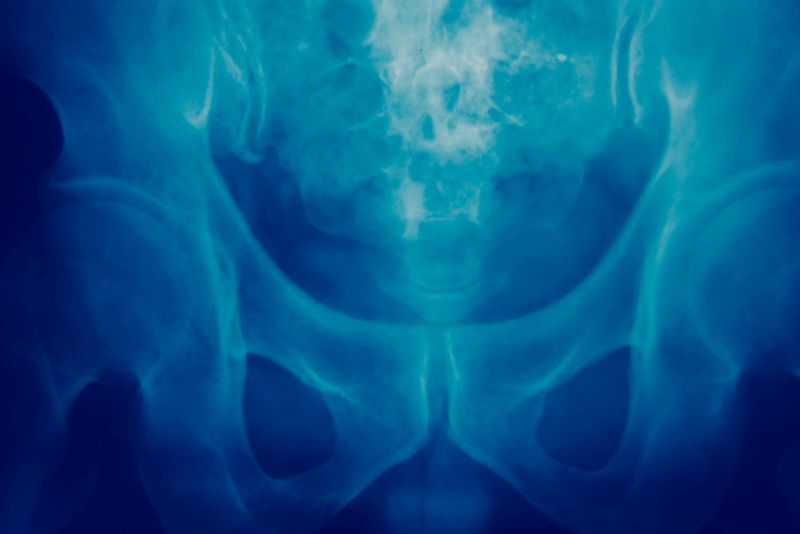

Najczęstszymi okolicami układu kostnego, w których lokalizują się ogniska przerzutowe raka są: kręgosłup, miednica, żebra, mostek, kość udowa, ramienna i kość czaszki.

Przerzuty raka do kości rozwijają się najczęściej w okolicy lędźwiowej kręgosłupa, następnie w jego odcinku piersiowym, kościach miednicy, żebrach, kościach udowych i ramieniowych.

Bóle nowotworowe wynikające z rozwoju guza w okolicy kości miednicy nasilają się w ciągu miesięcy, stają się coraz bardzie ostre, a ich intensywność często wzrasta w nocy.